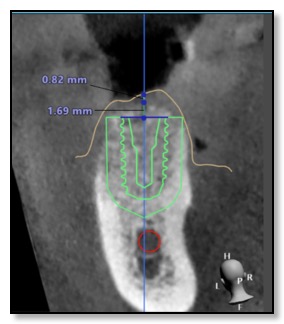

She combines these technologies with a 3D printer. Here's how it works: she creates a digital model of your jawbone structure and overlays it with a 3D scan of your teeth and gums. Then, she aligns it with your natural bite to evaluate your biting and chewing patterns. This helps her determine the best position for the dental implant.

After this process, she collaborates with her lab to 3D print a template that acts as a guide for placing the implant with utmost precision regarding depth, angle, and location.

Designing this surgical guide is a meticulous process that usually takes about three weeks. It's especially crucial for all-ceramic dental implants, as well as standard ones.

Now that the surgical guide is ready, placing the implant in your jawbone is pretty quick. To make sure the surgery goes smoothly, Dr. Tsai might prescribe a round of antibiotics before placing the implant. The actual placement, along with a confirmatory CT scan to double-check its position, usually takes about an hour. Dr. Tsai will numb the area with local anesthesia, use the surgical guide to line things up perfectly, use different bone drills, and secure the implant in place. Depending on your situation, she might attach a healing cap right away or use a smaller cover screw for healing later on. It takes around four to five months for the implant to integrate with the surrounding bone, a process called bone integration or healing. The exact duration depends on things like your oral cavity chemistry, any medications you're taking, and your overall health.